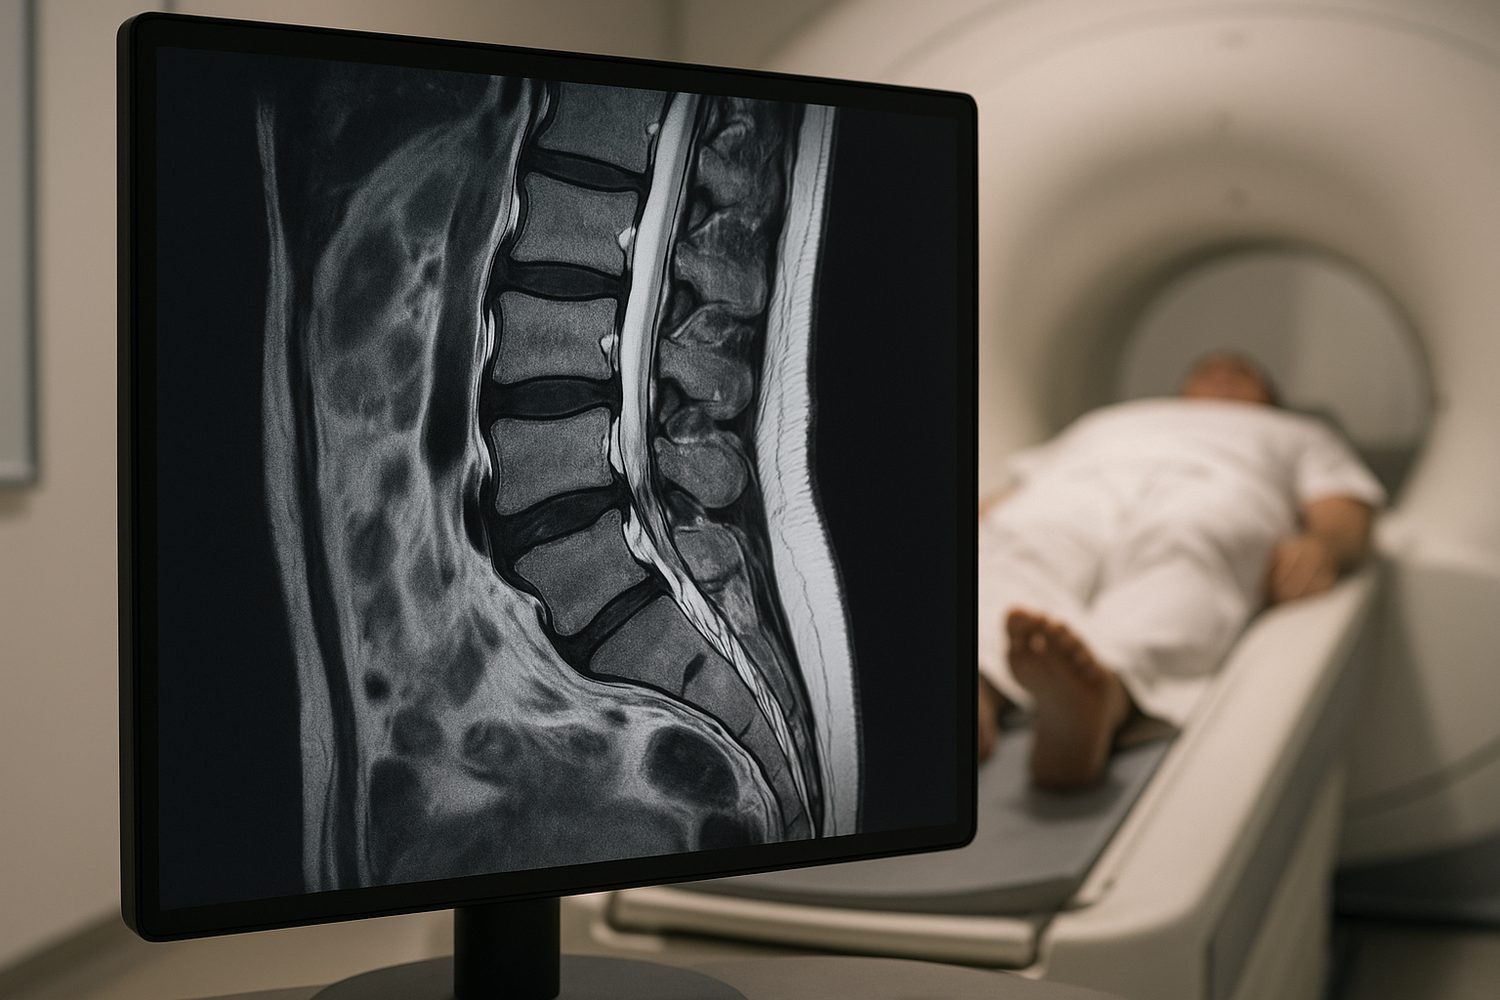

An MRI scan of the lower back is a sophisticated procedure that utilizes powerful magnets and radio waves to generate detailed images of the lumbar region, including the L1-L5 vertebrae, sacrum, coccyx, discs, nerves, ligaments, and spinal cord. Unlike X-rays or CT scans, which use ionizing radiation, MRI provides a safer alternative for examining soft tissues. The process begins with the patient lying down on a motorized table that slides into the MRI machine, which resembles a large tube. The scan typically lasts between 20 to 60 minutes, during which the patient must remain as still as possible to ensure clear images. In some cases, a contrast agent may be injected to enhance the visibility of certain structures.

A lower back MRI is instrumental in diagnosing a variety of conditions that can cause pain and discomfort. One of the most common findings is a herniated disc, where the cushioning material between vertebrae bulges out and presses on nearby nerves, causing pain and neurological symptoms. Spinal stenosis, a narrowing of the spinal canal that can lead to nerve compression, is another condition that an MRI can detect. Degenerative disc disease, which involves the gradual deterioration of the spinal discs, can also be identified through MRI scans. Additionally, MRIs can reveal the presence of tumors or infections, which, although less common, can have serious implications for health. Understanding these conditions through MRI findings is crucial for developing an effective treatment plan tailored to the patient's specific needs.